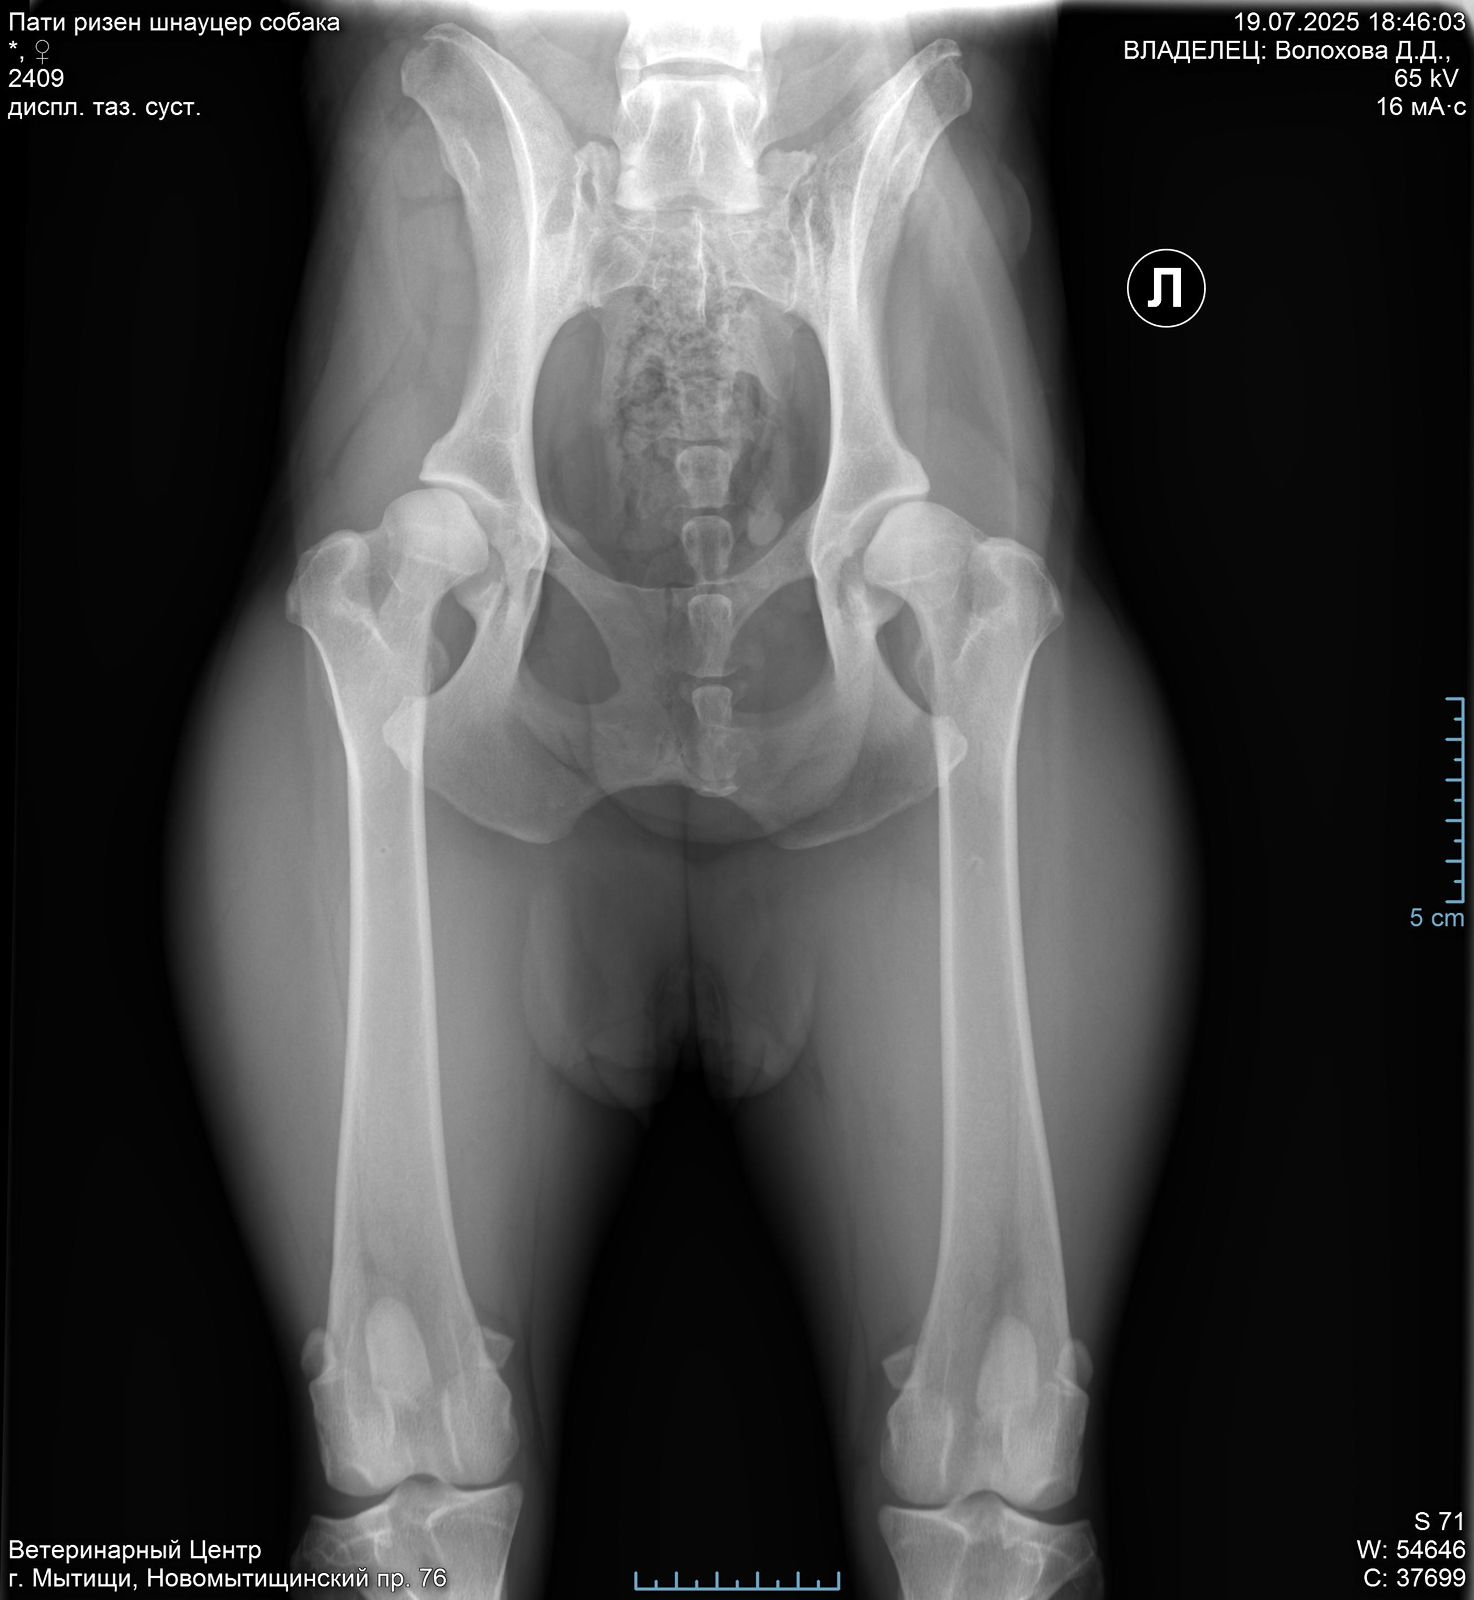

Ризеншнауцер Пати. 3 года

Москва (Пати оф Лайф). д. р. 05.02.2022

Задние ноги не идеал, но портить жизнь не должны.